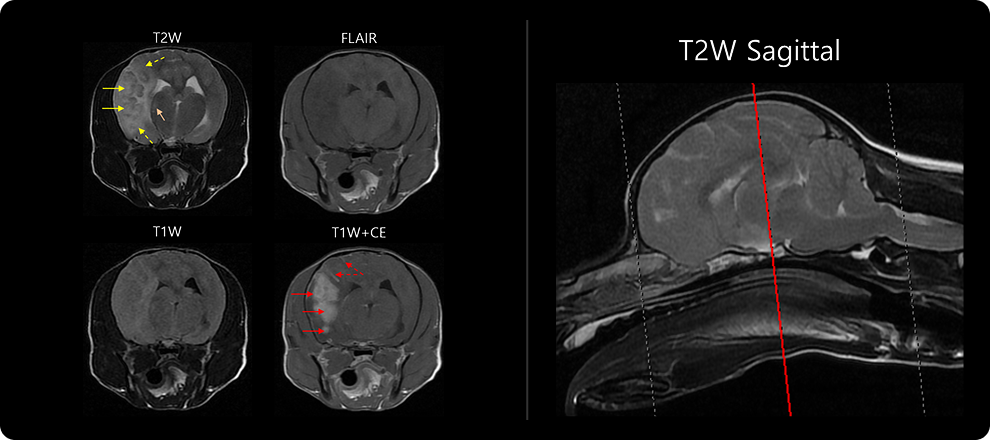

· MRI 검사

MRI 검사는 다양한 촬영 기법을 이용해 뇌질환을 감별하는 검사입니다. 뇌수막염에서는 뇌 부종성 병변, 괴사 병변, 뇌수막 변성 및 조영 증강, BBB(뇌혈관장벽) 손상 여부를 중점적으로 확인합니다. 이 단계에서 뇌와 척수의 구조적 이상, 염증의 위치와 범위를 파악합니다. 앞서 진행한 병력 청취 및 신경계 검사를 바탕으로 촬영 부위를 설정하며, 부위는 두개, 경추, 흉요추, 요천추 등으로 나뉩니다.

1-1 1-2 1-2 1-2

비감염성 뇌수막염은 아래와 같은 조직검사상의 분류로 분류되나, MRI 검사 상에서 분류는 한계가 있으며 MRI 상의 병변을 통해 질병 계통을 추정하게 됩니다.

• GME (Granulomatous Meningoencephalitis) 과립세포성 염증

• NME (Necrotizing Meningoencephalitis) 괴사성, 뇌회백질 위주 병변

• NLE (Necrotizing Leukoencephalitis) 백질 우세, 비대칭 병변